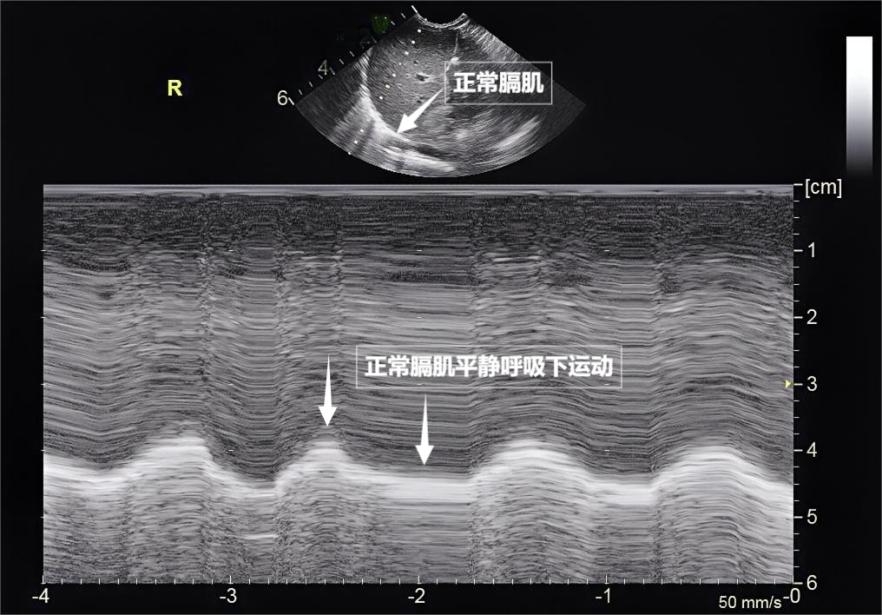

Breathing may seem simple, but it is actually a "team exercise" involving the precise coordination of multiple muscle groups. Lung ultrasound not only allows observation of lung morphology but also, through real-time dynamic imaging, "captures" the activity of these breathing muscles, providing a unique perspective for assessing respiratory function. The diaphragm is the "commander" of the breathing muscles, located between the thoracic and abdominal cavities. During quiet breathing, the diaphragm contracts and descends, expanding the thoracic cavity, naturally drawing air in; during exhalation, the diaphragm rises, and lung elasticity completes exhalation. Under ultrasound, the diaphragm appears as a smooth arc, moving up and down in a rhythmic pattern (see image below). The external intercostal muscles are the "elevators of the intercostal spaces," lifting the ribs during contraction, expanding the anteroposterior diameter of the thoracic cavity, and assisting in inhalation. This "golden duo" accounts for over 70% of the work in daily breathing, serving as the "main force" for maintaining respiratory function.

Image shows normal diaphragm ultrasound appearance